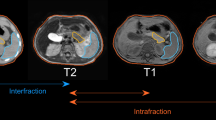

Inter-fractional and intra-fractional anatomical variations can introduce significant errors in dose delivered by radiation therapy. The impact of respiratory motion should not be ignored as respiration can induce both rigid body translation/rotation and organ deformation. The 3D dose distribution does not fully represent the dose accumulated by a moving tumor [25]. 4D dose calculation considers the changing beam aperture and the changing anatomy. It strongly depends on the patient’s respiratory cycle and therefore should be performed explicitly on a patient-specific base. In this study, for the 4D dose calculation, we used the concept presented by Ehrbar et al. [25].

The respiratory cycles of all the patients were divided into 10 breathing phases, according to the 4DCT. The original treatment plans (for ITV and tumor tracking concept) were divided into angular segments, which were temporally assigned to the breathing phases. This procedure was done by using in-house MATLAB scripts [25, 39].The created sub-plans were imported back to the treatment planning system and calculated on the different breathing phase. For the tumor tracking concept, the sub-plans were calculated on the different phase CT image set while the beam isocenter was shifted according to the current center of volume position for the GTV to simulate adaptive motion compensation. Subsequently, 4D dose accumulation was performed in MIM Software.

The dose accumulation was performed against the initial contouring phase and the other CT phases were registrated to this one phase using deformable image registration. Following, the dose distributions at other phases were summed up to the dose distribution at reference CT to make 4D dose accumulation [39]. The resulting accumulated 4D dose distributions were recorded for the GTV volume and the OARs of the reference phase.

In Table 2, the two motion management techniques are compared using dosimetric parameters of the 3D and 4D dose calculations. The target dose parameters are additionally shown in Fig. 2. There is a clear dosimetric advantage for tumor tracking, regarding the tumor coverage (D 95% ) in both, 3D and 4D dose calculation. Additionally, many of the OAR dose parameters such as duodenum, stomach, and liver D mean showed a significant improvement with tracking in 3D and 4D dose. There were also cases in which significant OAR dose reduction was only observed in the 4D dose distribution (bowel, left and right kidney D mean ), or the 3D dose distribution (bowel D 0.1cc ). Furthermore, highly correlated (rho ≥ 0.71), in absolute values, and significant (p<0.05) relationships were observed between the 3D dose difference (3D Tracking −3D ITV ) and the 3D tumor motion for the bowel D mean (rho=−0.73) and the target volume Dmean (rho = 0.73). No significant results were found for the correlation coefficients investigating the 4D dose differences.

Figure 3 shows dose-volume histograms (DVHs) for 3D and 4D dose calculations. The data is presented for two typical patients, patient 1 with pancreatic motion 11.2 mm and patient 7 with pancreatic motion 2.1 mm. For patient 1 there is an obvious gain in the dose coverage of the tumor and OAR dose sparing with tumor tracking approach. However, for patient 7 minimal improvements were observed regarding the tumor coverage and the OAR dose reduction. Additionally, using the ITV concept for patient 1 the 3D dose results in an overestimation for all OARs in comparison with 4D dose calculation. On the other hand, for the same patient using the tumor tracking approach almost no difference between the two dose calculations is noticed with the exception for the dose to the duodenum.

Dose-volume histograms (DVHs) for the target volume (TV), PTV and GTV, and also for the organs at risk (bowel, duodenum, liver, and stomach) for both dose distributions (3D and 4D) and motion management methods (the ITV concept and tumor tracking approach) in case of patient 1 (pancreatic motion: 11.2 mm) and patient 7 (2.1 mm). Target volume: ITV (ITV concept); GTV (tumor tracking approach). 3D = three dimensional; 4D = four dimensional dose. ITV = internal target volume concept; track = tumor tracking approach